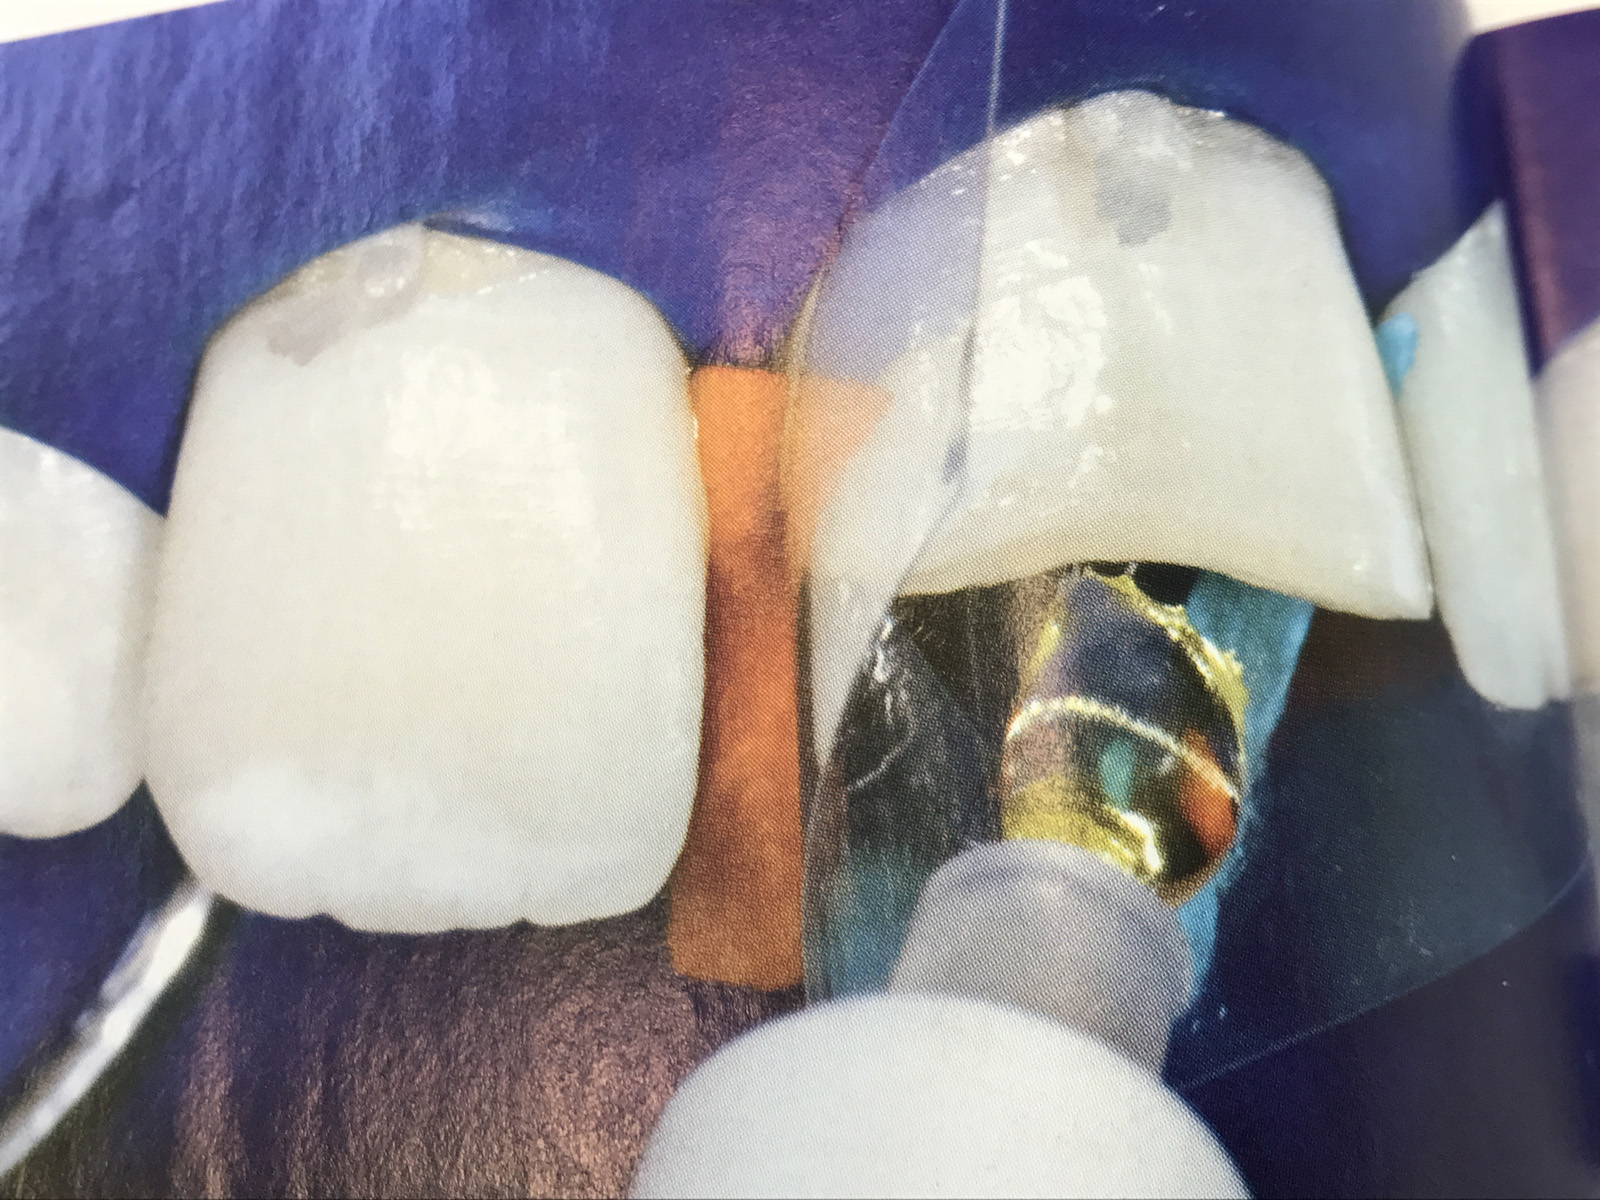

Frattura coronale conseguente ad un trauma sportivo.

Alla valutazione iniziale non è stata rivelata sintomatologia dolorosa di 2.1 e il dente ha risposto positivamente al test con cloruro di etile.

Dopo una valutazione clinica e radiografica si è deciso di ricostruire l'elemento dentario mediante una riabilitazione conservativa diretta con metodiche adesive utilizzando il sistema restaurativo di recente formulazione Venus Diamond.